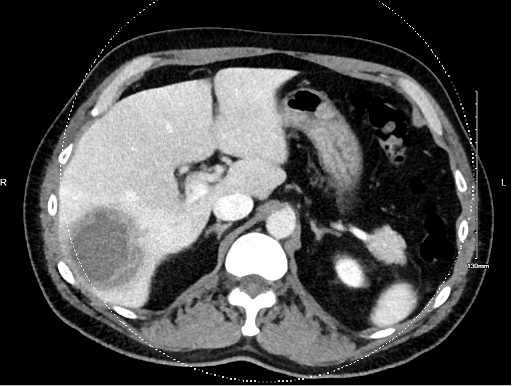

Diagnostic Testing. Laboratory findings were significant for mild leukocytosis with a white blood cell count of around 11,000 cells/μL with neutrophilic dominance, and an eosinophilic count that was within normal limits. The patient’s hepatic enzymes were also within normal limits. An ultrasound of the gallbladder was negative for an acute biliary process. The ultrasound of the liver was remarkable for heterogenous right hepatic mass measuring up to 6.6 cm (about 2.6 in) with associated peripheral vascularity and no significant cystic component, which is most concerning for a neoplastic process. Computed Tomography (CT) of the abdomen and pelvis was performed for further characterization (Figure 1). The imaging confirmed the diagnosis of a hepatic abscess however, we did not know whether the etiology was amoebic or pyogenic.

Fig. 1. Initial CT scan showing hepatic abscess.